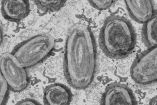

OPS pide no bajar la guardia ante covid y alerta sobre brotes de viruela símica y cólera

Con 460 casos, en Tabasco preocupa más el dengue que la viruela de mono

Confirma Coahuila primer caso de viruela del mono

La Secretaría de Salud de Coahuila, confirmó el primer caso de viruela del mono, en una persona originaria del Estado de México.

Vigilan caso de menor de 9 años sospechoso a viruela símica en Tamaulipas

De acuerdo con la Secretaría de Salud de Tamaulipas, será este viernes cuando se den a conocer los resultados de la prueba para detectar si el menor es portador de la contagiosa enfermedad.

Suman 3 casos de viruela símica en Chiapas

La Secretaría de Salud en Chiapas, dio a conocer que se detectaron 3 casos de viruela símica. El primer caso ya fue dado de alta, del hospital Gilberto Gómez Maza en Tuxtla Gutiérrez.

Monitorean a seis trabajadores por contacto con turista positivo a viruela símica en Playa Miramar

Los seis trabajadores habrían atendido al vacacionista de Nuevo León, que visitó el máximo paseo turístico sur de Tamaulipas a mediados de julio.